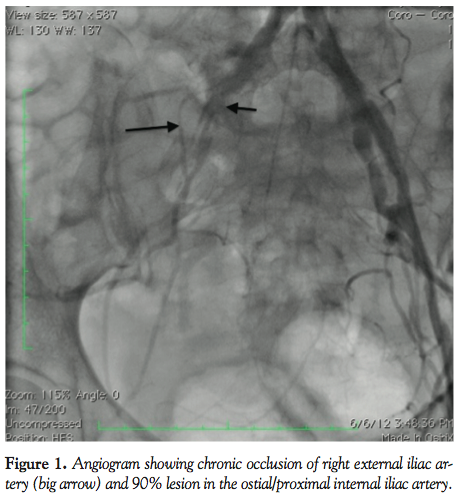

We did have a 47-year-old black female patient with hypertension, diabetes mellitus, hyperlipidemia, and coronary artery disease who presented with severe claudication of her right thigh and calf on walking 10 to 15 feet and abnormal ankle-brachial index of 0.59 on the right lower extremity. Selective angiography of the right lower extremity showed a patent CIA and chronic total occlusion (CTO) of proximal and mid EIA and 90% lesion of IIA ostial-proximally (Figures 1 and 2). Due to limiting symptoms, it was decided to intervene on the right EIA occlusion.